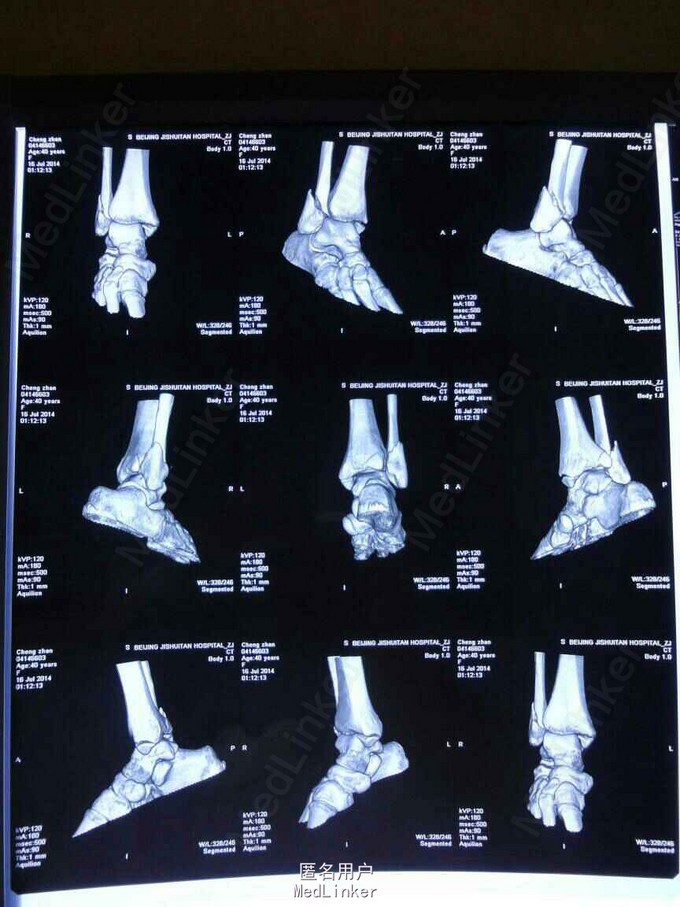

患者女,40岁。 主诉:右踝关节刺痛,活动受限6小时。 病史:患者6小时前走路时不慎扭伤右踝,伤后患者来我院门诊,门诊医师以‘’右踝关节骨折‘’诊断收入院,现患者无发热,饮食正常,大小便可。既往健康。

查体:患者生命体征正常,踝关节肿胀、畸形,内、外、后踝压痛阳性,有骨擦感,右踝关节功能障碍。 辅查:旋后外旋型踝关节骨折脱位

诊断:踝关节骨折脱位 ( 旋后外旋型 ) 治疗:切开复位内固定

随访:随访1年。 讨论:后踝骨折块较小故可不作固定。不会影响预后功能恢复。